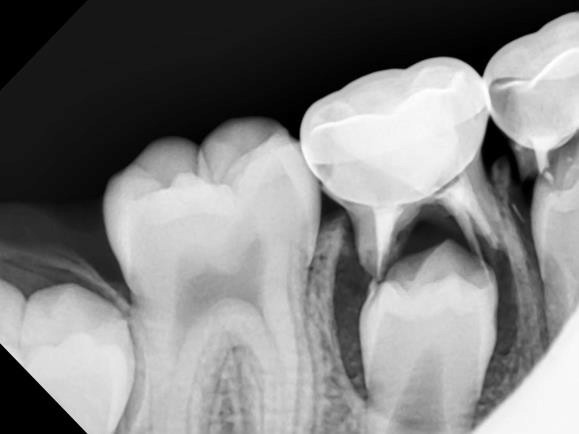

Dental sealants are thin, plastic coatings that seal over the narrow grooves found on the chewing surfaces of back teeth (molars and premolars).

When placed perfectly on these deep pits, sealants can prevent a significant amount of tooth decay (cavities) by protecting sensitive tooth surfaces from acid that causes cavities.

Dental sealants function much like sealing cracks in a driveway or on the sidewalk. The grooves in the chewing surfaces of back teeth are sealed so that food particles and bacteria will not settle within the fissures, causing cavities.

Application of sealants may be appropriate for some pediatric dental patients to prevent tooth decay in kids. However, they are not a substitute for brushing, flossing, and a healthy diet.